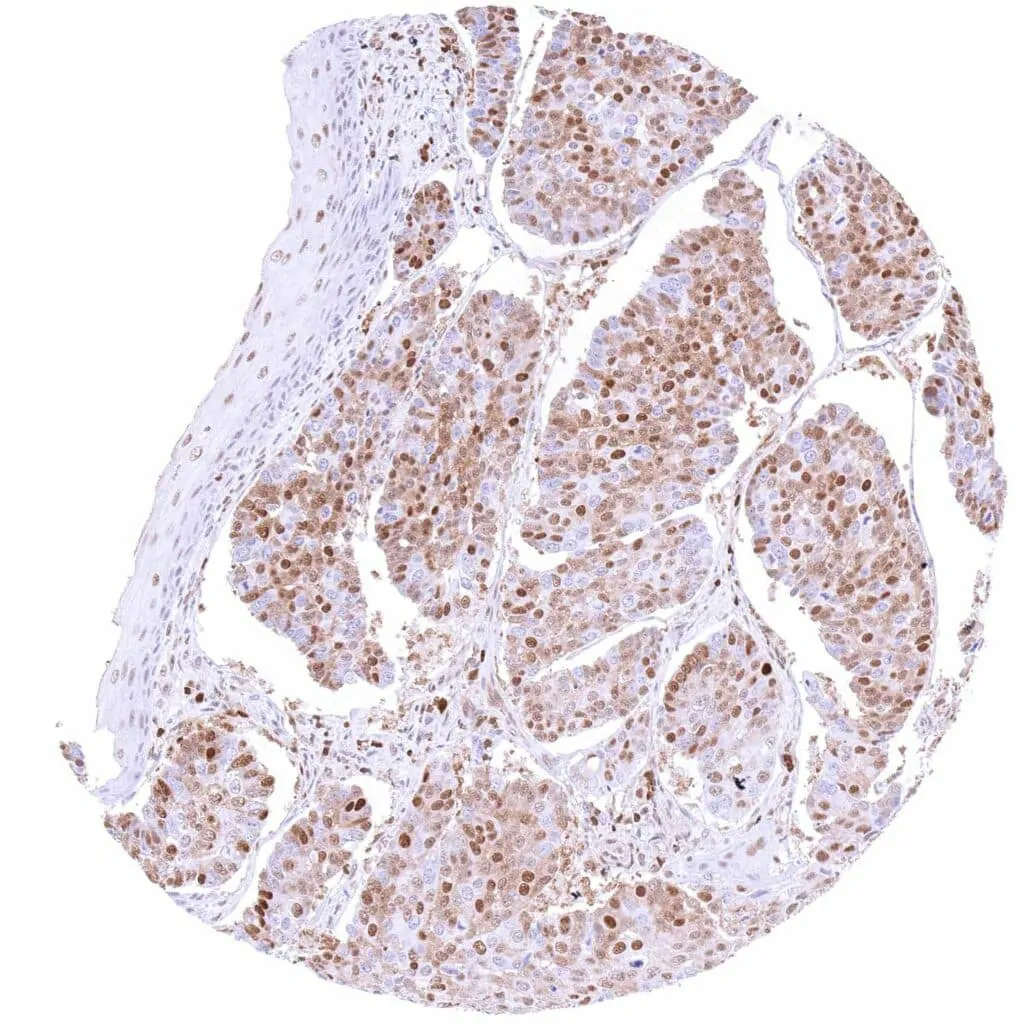

Prostate – Adenocarcinoma (Gleason 3+3=6) with moderate to strong, predominantly nuclear p27 positivity of tumor cells.